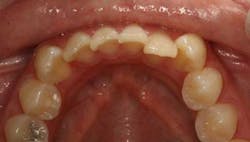

Let me clarify what Cfast is. Cfast allows us to provide limited orthodontic treatment that focuses on making the teeth the patients see (typically cuspid-to-cuspid) straighter. Because these teeth have single roots and the bone is not as dense, the treatment goes quickly so we can make this much more affordable relative to what many patients think about when considering traditional, comprehensive orthodontics. The dental laboratory determines actual placement of the brackets on the stone models, making this very exact. Placement is guided by a tray delivery system.

There is a lot we can do with the Cfast system. We can make space for improved implant dentistry. From a very practical standpoint, many of our patients want their lower anterior teeth straightened for better hygiene.

Some patients want a nicer smile and to get that smile we have to level the teeth, straighten the arch, or close diastemas.